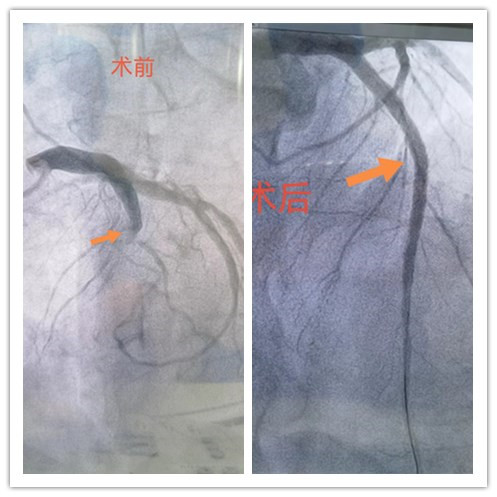

随后,心脑血管科征得患方同意后立即行冠脉造影检查,结果提示患者冠状动脉前降支近段堵塞,行血栓抽吸术+冠脉支架植入术。

术后,刘先生胸痛症状缓解,目前病情已相对平稳。